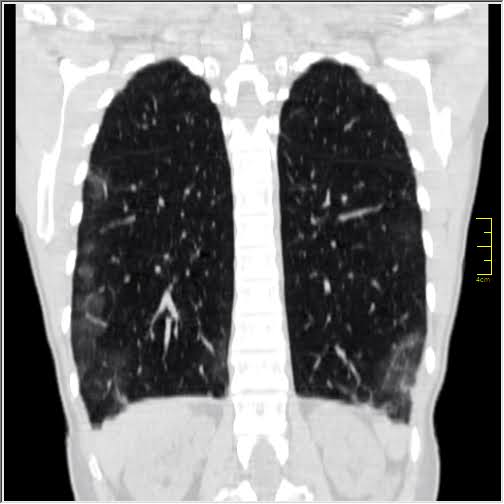

Pacijentkinja čije slike pokazujem (53) je prvo grafirana (Rdg) a nakon toga je urađen i CT pregled. Razlog za CT je bilo prisustvo izražene kliničke slike koja nije imala potvrdu na Rdg.

Na ovoj grafiji, ni uz pomoć mašte, nema elemenata zapaljenja pluća.

I dalje se na grafiji ne vidi. Šta smeta? Rebra i mišići. Zapaljenje nema takvu gustinu da bi se videlo na grafiji.